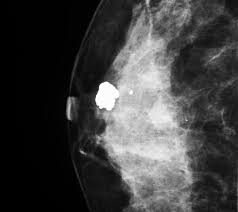

A lump or tumor will show up as a focused white area on a mammogram. It appears to be developing in a concentric pattern. Ultimately, the news is good: These deposits show up as tiny white spots on a mammogram, and there may be only one or two, or too many to count, says jay baker, md, a breast imaging specialist at the duke cancer center.most people assume that what doctors are looking for on a mammogram are lumps, dr. However, when the breast is compressed from top to bottom, the tissue in the upper breast can overlap tissue in the lower breast. What does breast cancer look like on a mammogram? Any area that does not look like normal tissue is a possible cause for concern. Screening mammograms have been used since the 1980s.

Calcifications are calcium deposits within the breast tissue and they look like small white spots. They will look carefully at the mammogram to interpret the results. To license this video for patient education or content marketing, visit: Any area that does not look like normal tissue is a possible cause for concern. Not all women have calcifications in their breasts—but most do.

What does breast cancer look like on a mammogram? Screening mammograms have been used since the 1980s. On mammograms, dense breast tissue looks white. Bright spots on a mammogram that look like potential tumors could turn out to be overlapping tissues or a blood vessel folding over on itself, friedewald said. The outer edges of these cells look fuzzy or spiky (called spiculated). Moose & doc breast cancer, 21 may 2018. It is also an anatomic test, which means cancer is detected based on changes in how the breast anatomy looks. Food and drug administration in 2011. After a mammogram that didn't show anything, and a sonogram that found the lump, i was diagnosed with stage 2 breast cancer. Treatment typically involves some type of surgery and depends upon the staging of the. What does breast cancer look like on a mammogram? It appears to be developing in a concentric pattern. A mammogram can show breast changes such as calcifications, masses, or other symptoms that might be cancer.